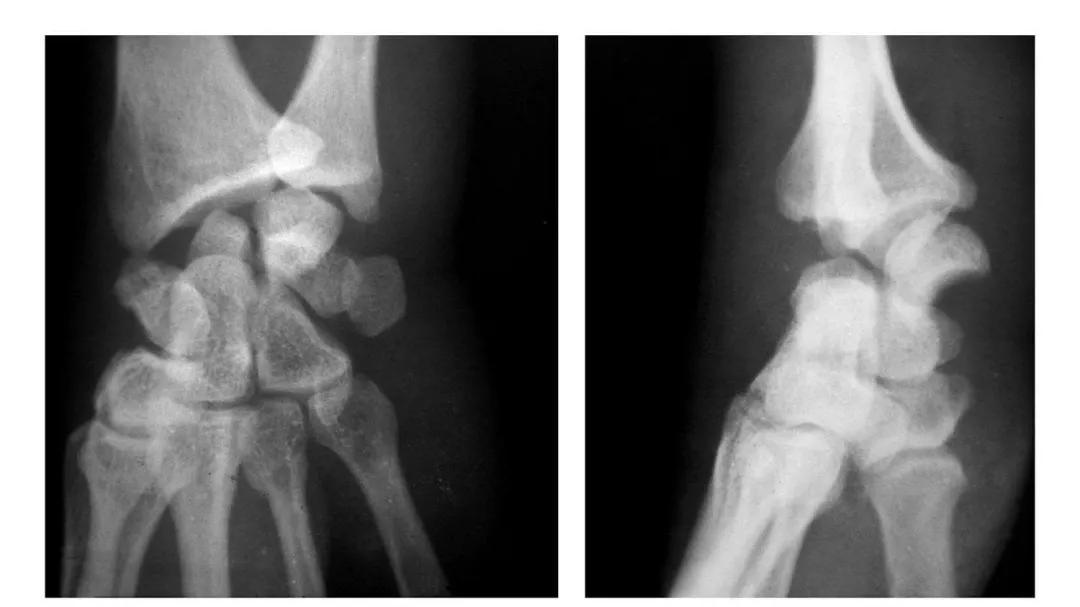

肱骨下端双髁骨折

例1:肱骨内髁及外髁骨折,该两髁骨块均呈向内、外翻转移位。

例2:肱骨内上髁Ⅲ度骨折并外上髁撕脱骨折。

例3:肱骨内上髁Ⅳ度骨折并外上髁撕脱骨折。